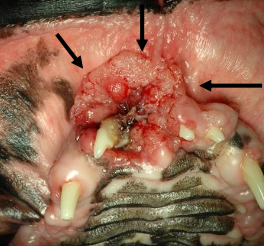

gross appearance = red, cauliflower, ulcerated

gross appearance = proliferative, ulcerated